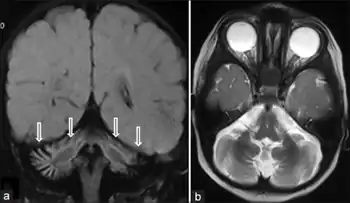

| SIL1-negative Marinesco-Sjögren syndrome a,b) MRI coronal and axial image shows cerebellar vermian and hemispheric atrophy | |

Diagnosis of MSS is based on clinical symptoms, magnetic resonance imaging (MRI) of the brain (cerebellar atrophy particularly involving the cerebellar vermis), and muscle biopsy.